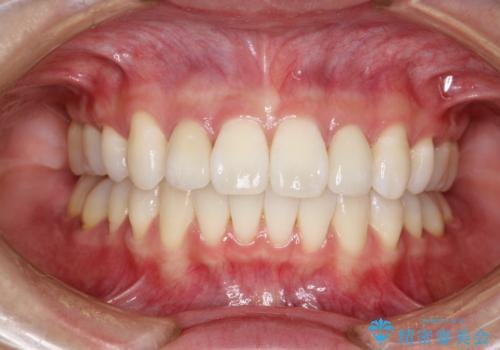

ワイヤー矯正とオールセラミックの組み合わせ治療

- 出っ歯と全体をきれいにしたいとのことで来院されました。

上顎の歯が全体的に前方に位置しているのと、前から2番目の歯が通常よりも小さい矮小歯という状態でした。

出っ歯をなおすために上顎の前から4番目の歯を抜歯して、引っ込めるのと、前から2番目の歯に通常の大きさのオールセラミックを装着して整った歯並びにすることにしました。

歯の大きさが通常と異なる場合は矯正治療で歯並びだけきれいにしても、整わないことがあります。

その場合はセラミックのかぶせ物を装着して歯の形を正常にすることで、さらに整った歯並びにすることができます。